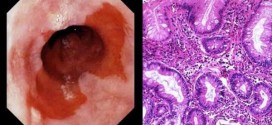

El esófago de barrett. El esófago es un tubo circular hueco de unos 22 centímetros de diámetro que conecta la cavidad bucal con estómago, que está colapsado entre las degluciones, pero la luz se distiende hasta 2,5 centímetros cuando pasan los alimentos. Cuando usted come, el alimento pasa desde la garganta al estómago a través del esófago (también llamado el …

La enfermedad pulmonar obstructiva crónica (EPOC) en ingles (COPD). El aire que usted respira baja por la tráquea a unas vías respiratorias llamadas bronquios, una especie de tubitos que se encuentran dentro de los pulmones. Dentro de los pulmones, los bronquios se ramifican en miles de tubos más pequeños y delgados llamados bronquíolos. Estos tubos terminan en racimos de sacos …